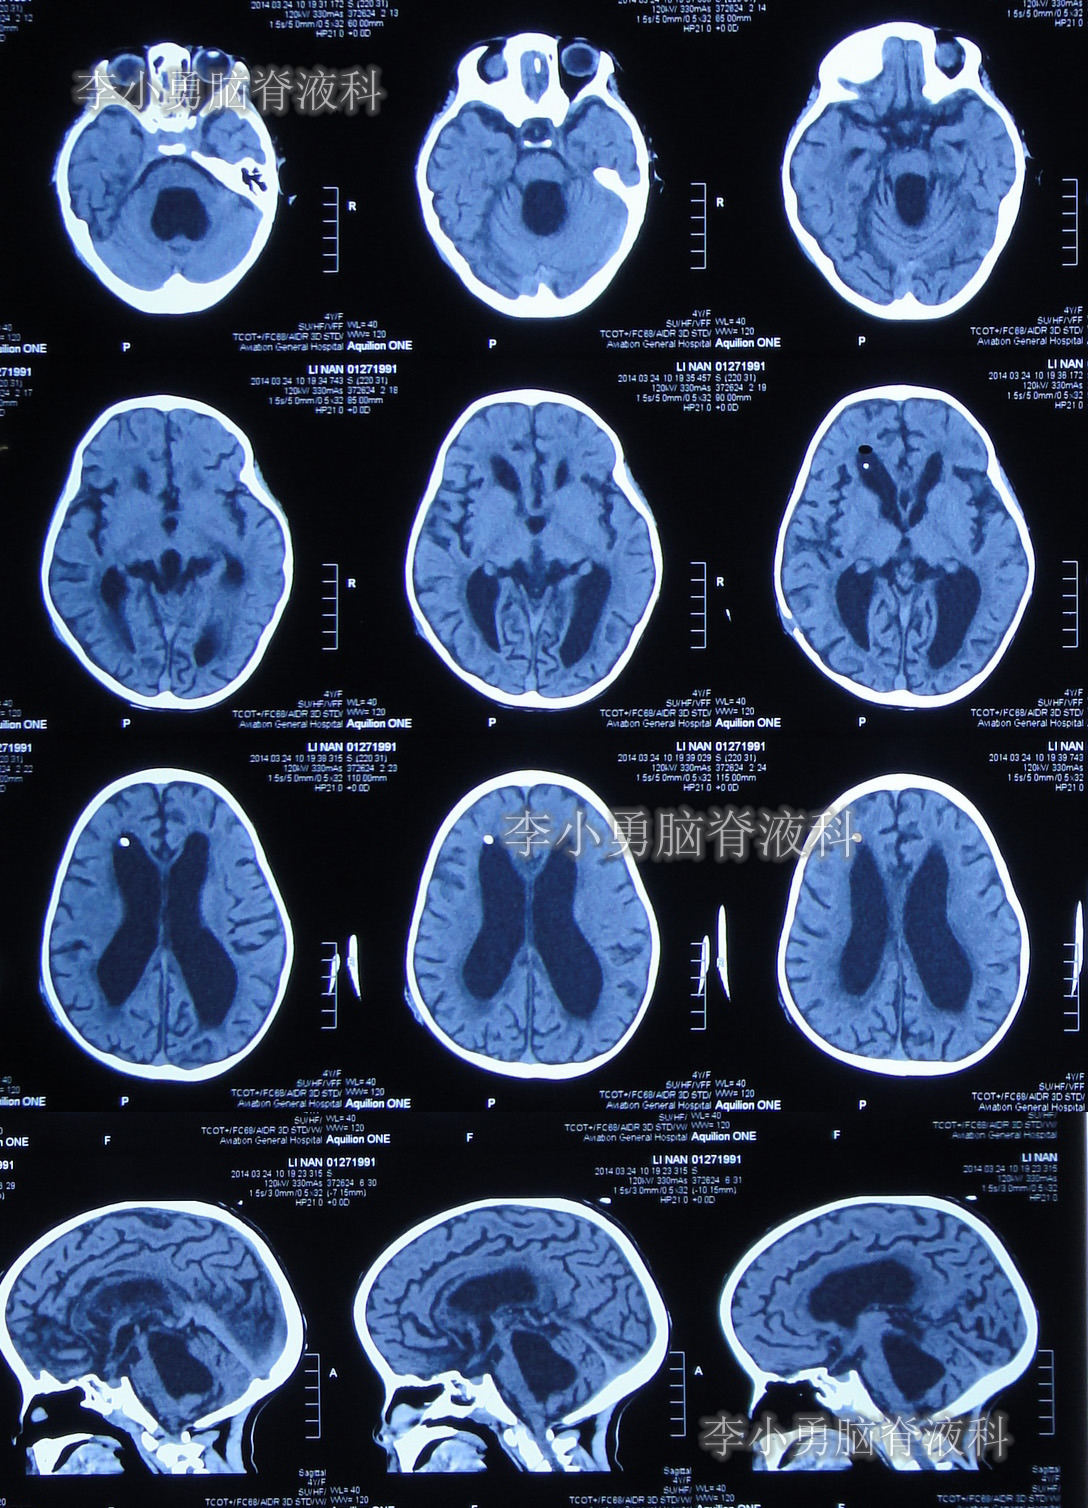

图-8:2014年3月24日头颅CT

住院治疗第28天即2014年4月14日,复查头颅CT示幕上脑室大小恢复到基本正常的状态,第四脑室再度显著缩小但仍稍大(图-11)。

图-11:2014年4月14日头颅CT